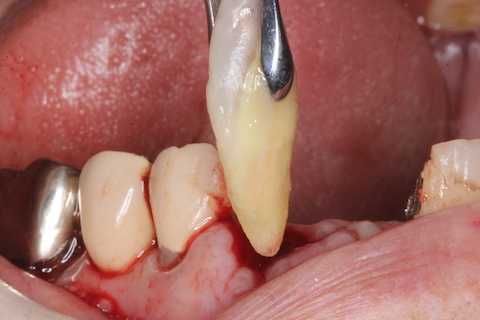

70代女性、右上4、歯根破折前回のつづきこの歯は1年ほど前に前医で治療を受けた時に、割れているので近いうちに抜歯になると言われたそうだ。そこはインプラントをしている歯医者だったので、インプラントは勧められなかったの?とお訊きしたら、そんなことは抜く直前しか言われないそうだw1週間後、とりあえず抜いてみた。かなり歯質は薄くなっていたので、抜くのも難しい。抜歯鉗子で握り潰してしまいそうだ。抜いて見てみると、完全離断ではなかったが、クラックがあるかもしれなかったので、抉り割ってみた。あとは綺麗にして、スクリューポストを入れて再建していくのだが、根尖口とは違うところにリーマーが飛び出して折れていた。また、根管充填材はFeS(硫化鉄)で黒くなっていた。これは硫酸塩還元細菌が生息していたということを意味しており、根管内は細菌で汚染されていたということだ。緊密な根管充填は垂直加圧法以外では見たことがない。所詮、人間のすることなどこの程度だ。これでは遅かれ早かれ歯はだめになってしまう。神経を取るなど最初からしないのが一番良いのだが、なぜしないのだろうか? 歯科医師は歯学部を卒業するまでに完全に洗脳されてしまうようだ。今日は再建から再植まで。根尖はリーマーが突き抜けて折れていた部分と、本物の根尖口らしいところを開拡して充填した。では時系列でどうぞ

70代女性、右上4、歯根破折前回のつづきこの歯は1年ほど前に前医で治療を受けた時に、割れているので近いうちに抜歯になると言われたそうだ。そこはインプラントをしている歯医者だったので、インプラントは勧められなかったの?とお訊きしたら、そんなことは抜く直前しか言われないそうだw1週間後、とりあえず抜いてみた。かなり歯質は薄くなっていたので、抜くのも難しい。抜歯鉗子で握り潰してしまいそうだ。抜いて見てみると、完全離断ではなかったが、クラックがあるかもしれなかったので、抉り割ってみた。あとは綺麗にして、スクリューポストを入れて再建していくのだが、根尖口とは違うところにリーマーが飛び出して折れていた。また、根管充填材はFeS(硫化鉄)で黒くなっていた。これは硫酸塩還元細菌が生息していたということを意味しており、根管内は細菌で汚染されていたということだ。緊密な根管充填は垂直加圧法以外では見たことがない。所詮、人間のすることなどこの程度だ。これでは遅かれ早かれ歯はだめになってしまう。神経を取るなど最初からしないのが一番良いのだが、抗生剤も普及しているにもかかわらず。なぜこんなことを100年以上もし続けるのだろうか? 歯科医師は歯学部を卒業するまでに完全に洗脳されてしまうようだ。今日は抜歯するまで、まずはレントゲン写真でのbefore/afterだ。beforeリーマーが折れこんでいるのが見えると思う。after抜歯はかなり手こずった。壊しそう。。抜歯窩は膿瘍を丁寧に搔爬し、洗浄しておくつづく

前回のつづきで、再植と化粧をする。さすがに歯なしでは寂しい。普通にズブズブと抜歯窩に再建した歯根を挿入する。あとは接着固定しながら、歯冠を再建していく。

前回のつづきで、歯根の再建と再植だ。歯根は裏表を逆に植え戻すことがあるが、やってみるとソケットにうまく戻らなかったので、やめることにした。綺麗にして既製のポストを入れて補強、再建していく。小さな破折片は使わなかった。歯根膜は失われているので、歯肉は下がるからだ。どうせ歯質が露出していれば虫歯になるだけだから、最初から充填しておいた方が良い。根尖口も開拡して充填する。準備ができたら再植する。